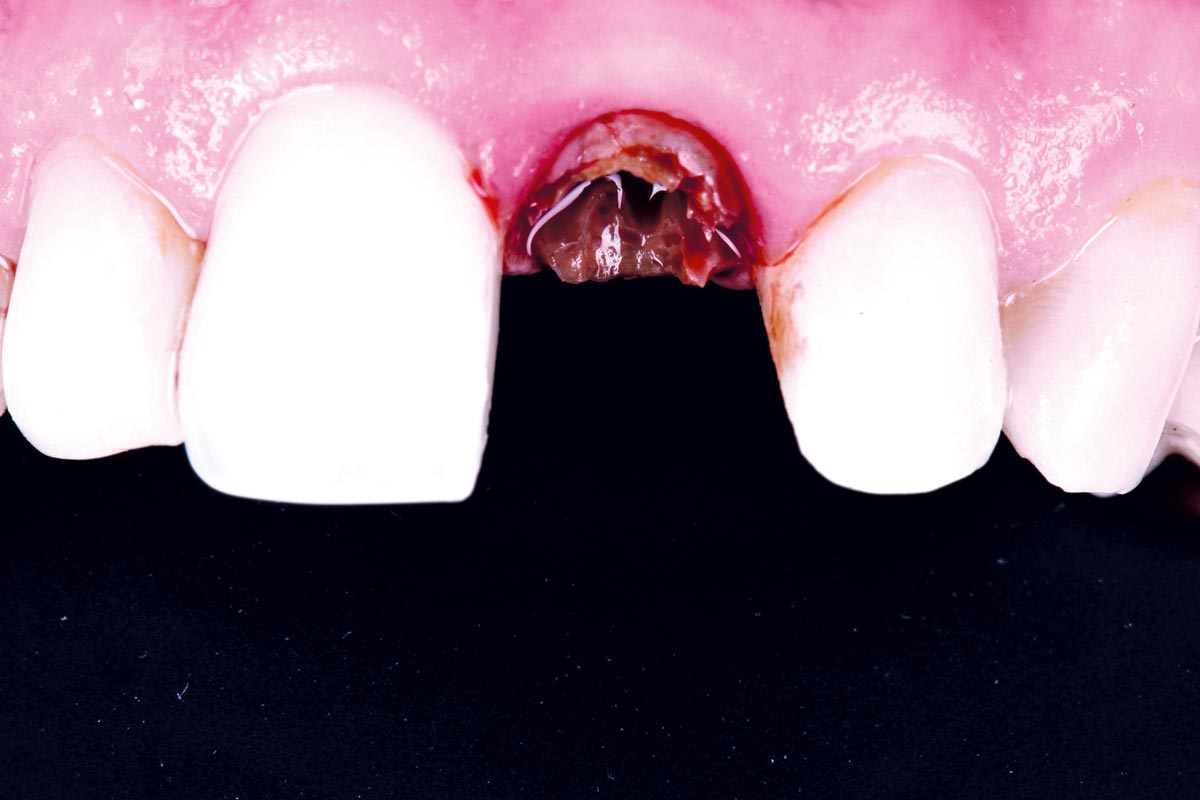

Initial clinical situation - Central incisors with dental destruction and periapical pathology